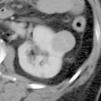

Objetivo. El oncocitoma es un tumor renal benigno, relativamente infrecuente. Hasta este momento su diferenciación radiológica del carcinoma de células renales se considera imposible, aunque hay escasos artículos en que se haya utilizado la tomografía computarizada (TC) trifásica. Los autores describen los hallazgos con TC trifásica en estos tumores, valorando si algunas características, aunque no diagnósticas, sí pudieran sugerir la posibilidad de este diagnóstico. Esto, en algunos casos, podría cambiar el manejo de los pacientes. Material y métodos. Se describen los hallazgos de TC trifásica en 10 casos de oncocitoma, vistos en 8 pacientes (un caso era multifocal-bilateral). En todos los casos el diagnóstico fue anatomopatológico, en la pieza de resección. Resultados. Todos los tumores fueron hallazgos ecográficos incidentales previos a la TC, presentando un tamaño muy variable, de 3 a 15 cm, con una media de 5,2 cm. El contorno era bien definido. Uno de los pacientes tenía tumores bilaterales (2 derechos y 1 izquierdo). Excepto en un tumor, el resto mostraban una cicatriz «estrellada» interna, que en un caso seguía un marcado patrón lobular. La captación tumoral de contraste fue ávida, con una media de 120 HU en fase arterial y 116 HU en fase excretora. La evolución de todos los pacientes fue buena, no detectándose recidivas postquirúrgicas. Conclusiones. Aunque la diferenciación con el carcinoma de células renales no puede hacerse con certeza, debe sugerirse la posibilidad de oncocitoma, fundamentalmente en tumores pequeños, con cicatriz central, ausencia de necrosis, falta de infiltración y un patrón de captación como el que se describe. Independientemente del tamaño, una morfología lobular del tumor también debe sugerir esta posibilidad.

Objective. Oncocytoma is a relatively uncommon benign kidney tumor. To date, it has been impossible to differentiate this tumor from renal cell carcinoma radiologically, although few articles report on the use of tri-phase CT in this tumor. We describe the triphasic CT findings in these tumors and evaluate whether some characteristics, although not sufficient to ensure the diagnosis, can suggest the possibility of oncocytoma. In some cases, this may lead to a different approach to the management of patients. Material and methods. We describe the tri-phase CT findings in 10 cases of oncocytoma in eight patients (one case was bilateral and multifocal). The diagnosis was made after histological examination of surgical specimens in all cases. Results. All the tumors were found incidentally at ultrasound examination prior to CT study. Tumors all had well-defined borders, and their size ranged from 3 to 15 cm, with a mean diameter of 5.2 cm. One patient had bilateral tumors (2 right and 1 left). All but one of the tumors had a star-shaped scar inside, with a marked lobular pattern in one case. All tumors showed avid uptake, with mean enhancement of 120 HU in the arterial phase and 116 HU in the venous phase. All patients evolved favorably with no post-surgical relapse. Conclusions. Although oncocytoma cannot be differentiated from renal cell carcinoma with certainty, the possibility of oncocytoma should be suggested in the case of small tumors with a central scar, without necrosis or infiltration, and an enhancement pattern as described here. Regardless of the size of the tumor, lobular morphology should also suggest this possibility.